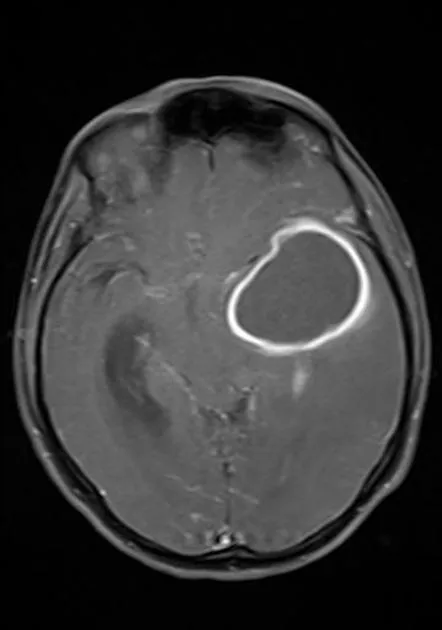

- Brain Abscess: Focal collection of pus within brain parenchyma.

- Imaging: CT/MRI shows characteristic ring-enhancing lesion.

- Stages: Early cerebritis → Late cerebritis → Capsule formation.

- Brain abscess: Ring-enhancing lesion on imaging; central necrosis, surrounding fibrous capsule.